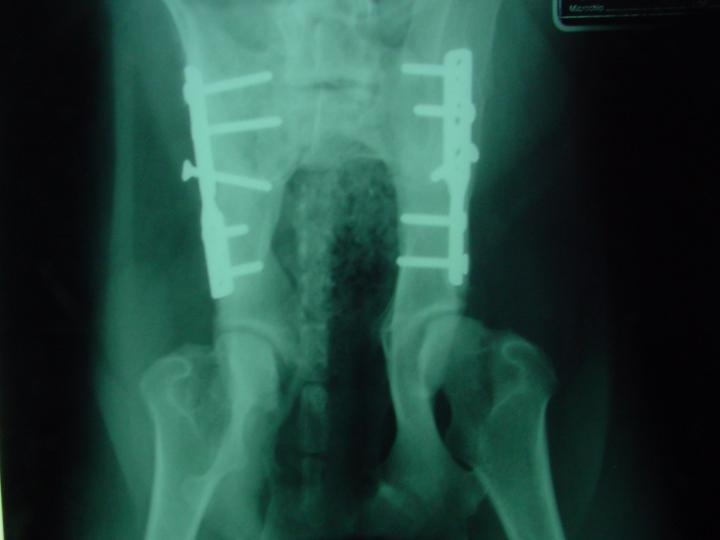

- Abordagem lateral do Ilium permite a osteotomia do Ilium e aplicação da placa Porte. Esta placa de ângulo preformado 20 ou 25 º de 7 furos e lateralização substitui a placa PCD (placa de compressão dinâmica AO/ASIF – 5 ou 6 furos e posteriormente a placa CPOP ( Canine Pelvic Osteotomy plate, Slocum de 6 furos).

Durante o primeiro mês aconselhou-se exercÃcio limitado e passeio à trela. Ao 2º e 3º mês foi progressivamente tomando a actividade normal. Observamos que no controlo radiológico imediato a cobertura acetabular se corrige muito pouco. Só ao fim de 4 semanas é que começamos a verificar um aumento da cobertura acetabular.